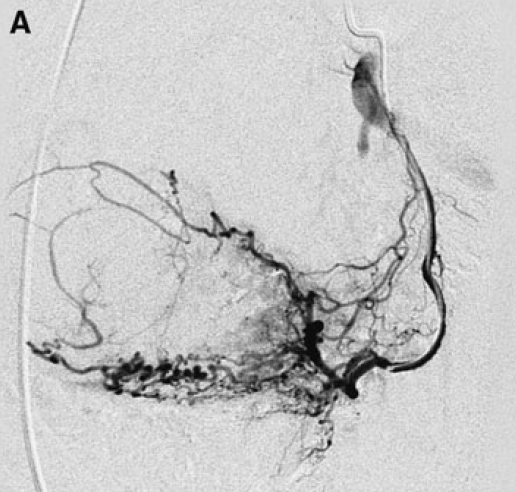

A Un artériogramme sélectif de l’artère utérine gauche. La position du cathéter était considérée comme légèrement trop proximale (l’extrémité au-dessus de l’origine des branches cervicovaginales) et a été corrigée pour l’embolisation.

B Contrôle final après instillation de 3,8 ml de microsphères Embozene de 500 micromètres. Le critère d’arrêt angiographique adéquat a été atteint (7).